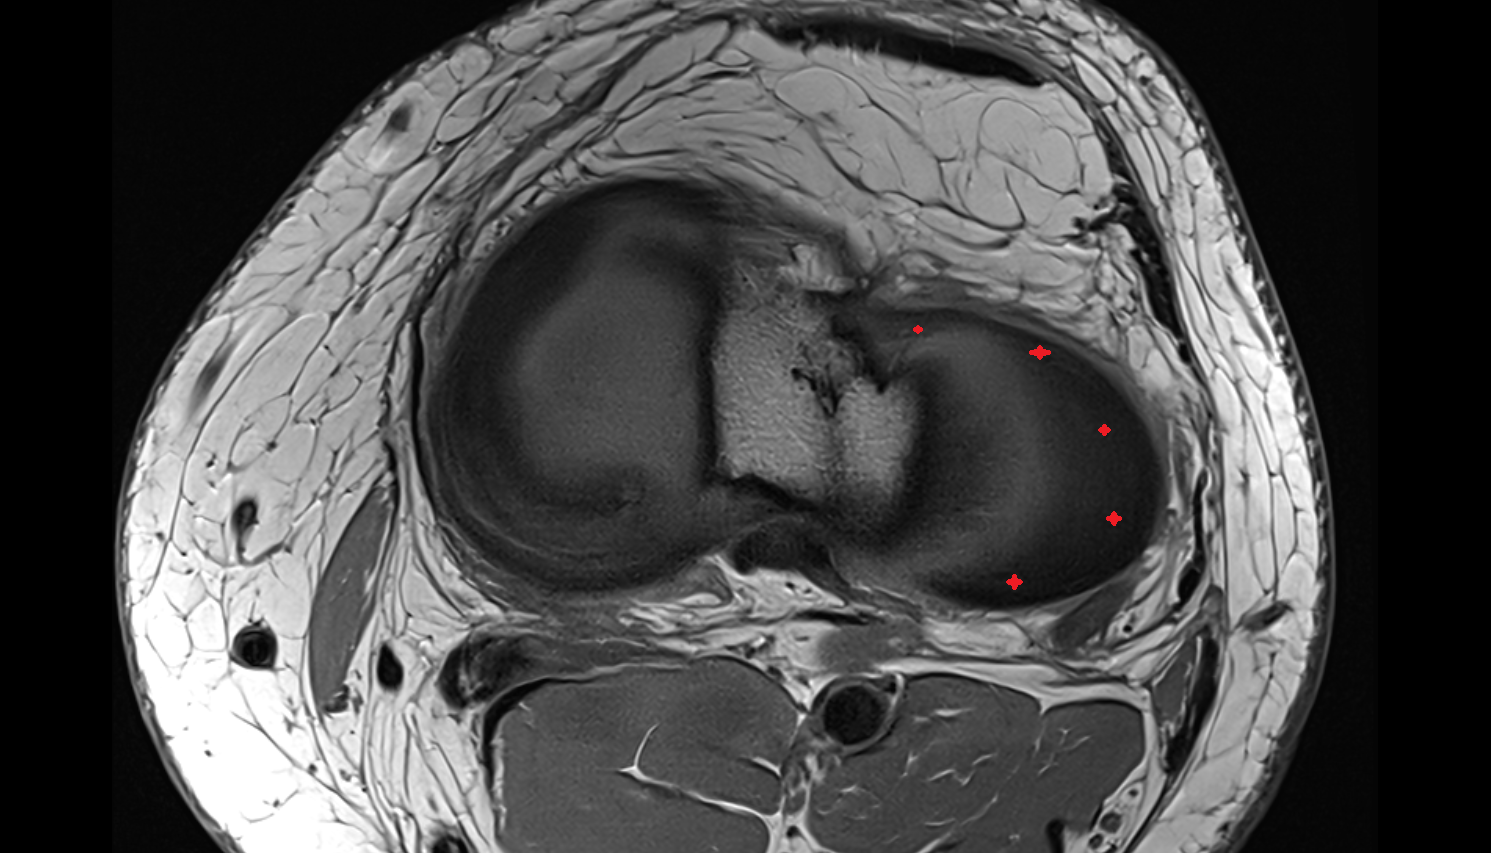

- Meniscus cartilage

- Medial meniscus

- Lateral meniscus

- Knee Joint